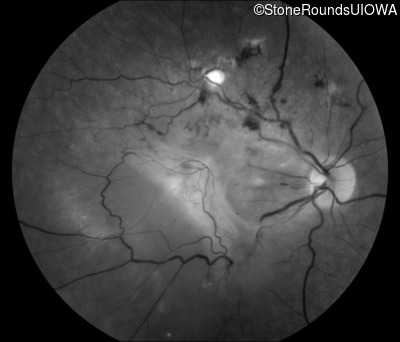

Fundus Photography - Right - 20/400 sc

Exemplar

Fundus Photography - Left - 20/250 sc